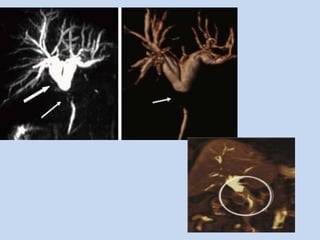

• In Cholangiocarcinoma :

• In hilar cholangiocarcinoma, it depicts the length of

APPLICATIONS • In Cholangiocarcinoma: - MRCP is very accurate in identifying the presence & level of neoplastic obstruction of pancreatobiliary tract. - In conjunction with conventional MR + MRCP and , when necessary MRA permits not only diagnosis but also staging of malignant tumors of pancreatobiliary tract.

• In hilarcholangiocarcinoma, it depicts the length of extra-hepatic bile duct involved by the disease as well as the proximal extent of the disease – an important factor in determining the resectability.